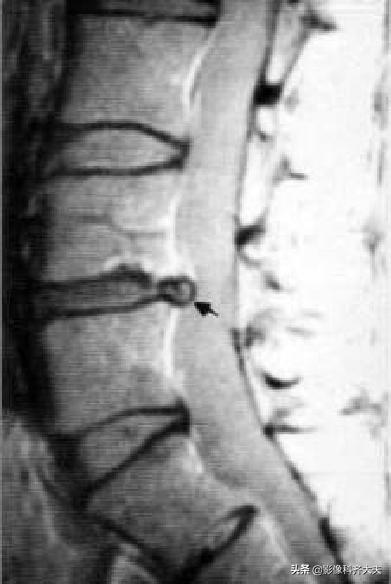

Schmorl结节(许莫氏结节)

Schmorl结节(许莫氏结节),是椎间盘退变时,软骨板变薄及玻璃样变,甚至消失。髓核经软骨板的薄弱或者缺损部疝入椎体内,在椎体内形成软骨结节。

是髓核于椎体上面或者下面形成的圆形或者半圆形的骨质凹陷区,其边缘有硬化。可对称见于相邻两个椎体的上下面,并且可以累及多个椎体。

可以说算是一种特殊类型的椎间盘突出。只不过不像普通椎间盘突出是突出于椎体后缘,而是突出到上下椎体里!

在影像上看,椎体上下缘弧形的凹陷或者骨性透亮区,伴有不同程度的边缘硬化,广泛硬化时椎体呈象牙质样。

许莫氏结节并骶管内囊肿